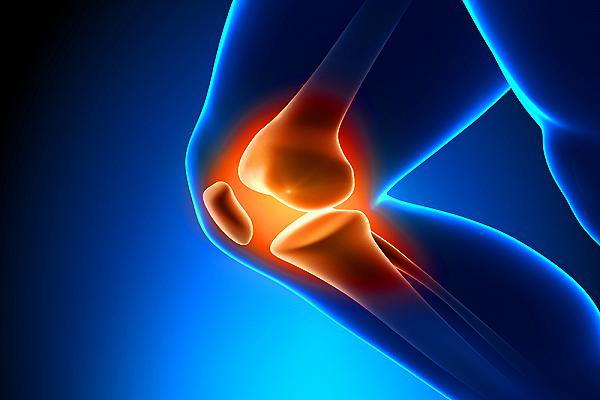

Fino agli anni ’90, il ricorso all’impianto di protesi al ginocchio significava anche per lo sportivo professionista la rinuncia forzata a qualsiasi disciplina sportiva, ma oggi la chirurgia ortopedica mini invasiva, grazie alle nuove tecnologie protesiche, consentono al paziente di riprendere l’attività fisica, seppure entro certi limiti.

Quando è necessario ricorrere alla protesi ginocchio mini invasiva?

Nei casi di artrosi al ginocchio (gonartrosi) primaria o secondaria per i quali ricorrere alla terapia farmacologica non basta più, quando il dolore acuto, la rigidità, la funzionalità articolare seriamente compromessa rendono la malattia invalidante.

La protesi al ginocchio è indicata anche nei casi di artrite reumatoide o condrocalcinosi, responsabili della degenerazione dell’articolazione oppure nelle patologie traumatiche.

| Il parere del Dott. Michele Massaro Abbiamo chiesto il parere di uno dei massimi esponenti e specialisti in Italia di protesi al ginocchio e anca mini invasiva, il Dott. Michele Massaro, chirurgo ortopedico delle Cliniche Humanitas.-È realmente possibile riprendere a fare sport con una protesi al ginocchio?“La protesi monocompartimentale mini invasiva – che sostituisce un solo compartimento dei tre che costituiscono il ginocchio (mediale, laterale e femoro-rotuleo) – può consentire al paziente di riprendere l’attività fisica, sia che si tratti di una protesi del compartimento mediale (più frequente come incidenza) che degli altri compartimenti. Ovviamente, il paziente deve avere un peso forma, deve aver recuperato completamente il range di mobilità articolare, il tono muscolare e deve essere stata corretta dal chirurgo la deviazione assiale esistente prima dell’intervento.-Si può fare qualsiasi tipo di sport?“Di solito il consiglio è quello di limitarsi alle discipline sportive a basso impatto (nuoto, golf, walking) mentre quelle ad alto impatto (calcio, basket, corsa), seppur teoricamente possibili, possono portare ad un’usura precoce del polietilene, a traumi, oltre che ad una precoce mobilità delle componenti protesiche”. |

La protesi al ginocchio monocompartimentale, ripristinando la funzionalità dell’articolazione e riducendo il dolore, migliora la qualità della vita e spinge il paziente a riprendere l’attività fisica con molto entusiasmo, ma è importante sottolineare anche quali sono i rischi connessi alla ripresa dell’attività sportiva da parte di un paziente con protesi al ginocchio: instabilità articolare, usura precoce e scollamento della protesi.

Per chirurgia mini invasiva s’intende, in sostanza, una tecnica chirurgica che rispetta il corpo ‘invadendo’ al minimo l’anatomia del ginocchio: interviene per sostituire con la protesi soltanto le zone irrimediabilmente danneggiate risparmiando il più possibile quelle sane.